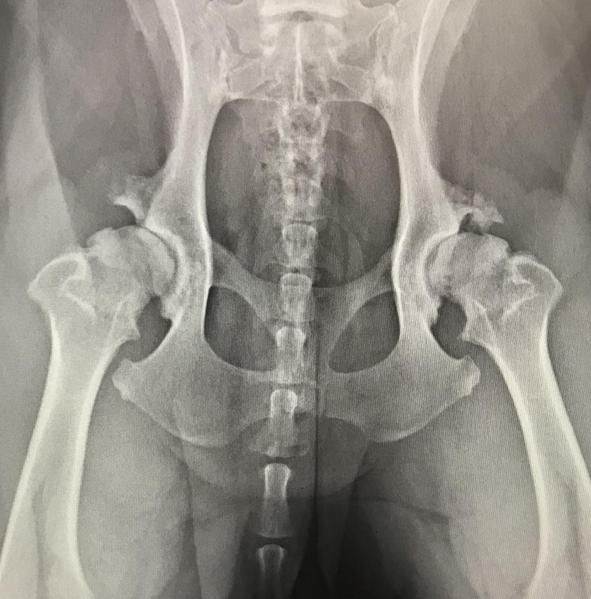

X-ray imaging remains an invaluable diagnostic tool, offering essential insights into heart, lung, digestive, and urinary tract diseases. For skeletal evaluations—whether assessing fractures, degenerative changes, growth abnormalities, or congenital malformations—X-rays are still the preferred method.